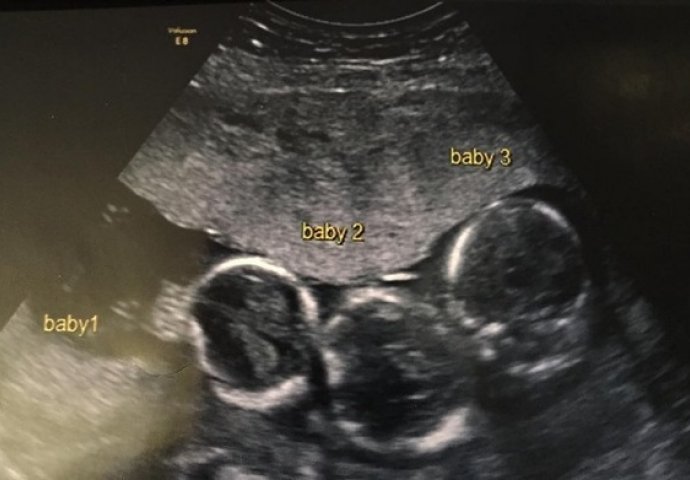

Becki- Jo Allen i njen dečko Liam Tierny žive u Liverpoolu u Engleskoj sa svojom kćerkicom pod imene Idniana.

Becki je od samog početka trudnoće imala problema sa jutarnjim mučninama, te joj je rečeno da će trudnoća biti zahtjevna i teška.

Željno su iščekivali prvi ultrazvuk kako bi otkrili u kakvom je stanju beba, te kojeg je spola.